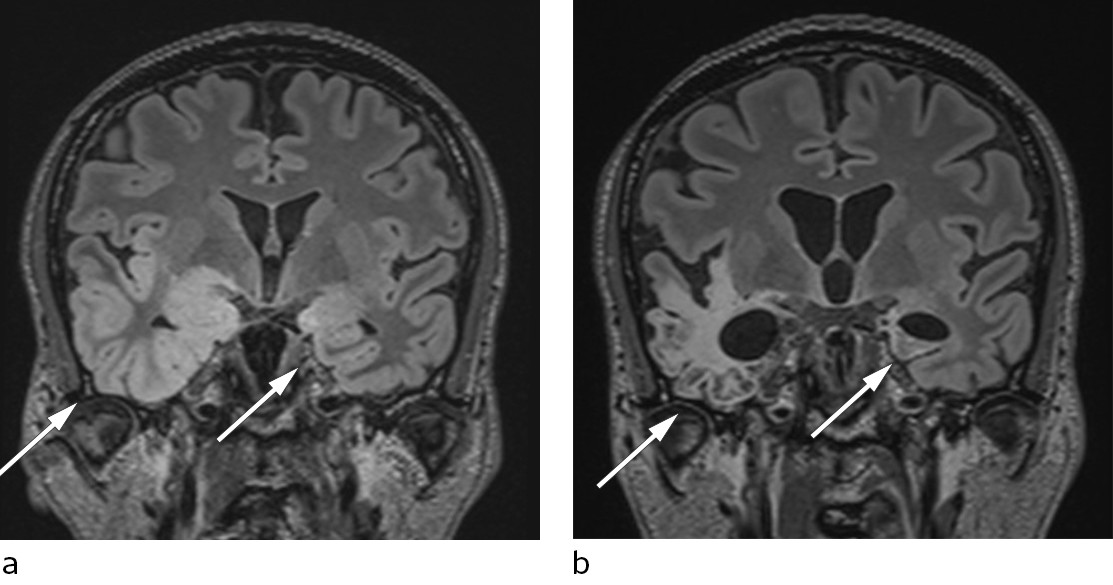

Denne viste patologisk langsom bakgrunnsaktivitet og utbrudd av deltaaktivitet i temporale regioner. Funnet var forenlig med encefalitt (6, 7). MR-undersøkelse av hodet, som ble utført seks dager etter innleggelsen, viste utbredte forandringer temporalt, inkludert i hippocampus, hvilket er typisk for herpesencefalitt (8) (figur 2, figur 3a).

En uke etter oppstart med immunglobulinbehandling ble det bekreftet høyt titer av antistoff mot NMDA-reseptor i pasientens spinalvæske. En ny cerebral MR-undersøkelse tatt fire uker etter den første, viste økende høysignalforandringer temporalt bilateralt. Dette funnet er ikke spesifikt for verken herpesencefalitt eller autoimmun encefalitt (11).

Tilstanden stabiliserte seg etter noe tid, og man forsøkte rehabilitering i flere omganger, men pasienten gjenvant aldri tilstrekkelig funksjon til å kunne bo hjemme. Han bor nå i omsorgsbolig med stort oppfølgingsbehov. En ny MR-undersøkelse 4,5 måneder etter symptomdebut viste omfattende skade i temporallapper (figur 3b).

Hos vår pasient var det nok allikevel den virale encefalitten som ga størst permanent skade (figur 3a og b).